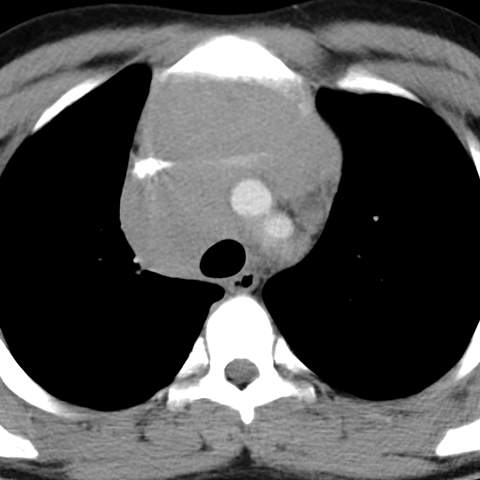

Diffuse Mediastinal Lymphadenopathy in Hodgkin's (Chest CT)